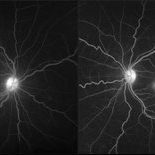

Cystoid Macular Degeneration

Feb 1 2023 by Kachelle Brown

Fluorescein Angiogram of a 56 year old woman with bilateral Cystoid Macular Degeneration. Patient vision was 20/60 OU.

Photographer: Kachelle Brown OMA, Retina Specialist of Michigan

Condition/keywords: cystoid macular degeneration, cystoid macular edema (CME), FA late phase, fluorescein angiogram (FA)